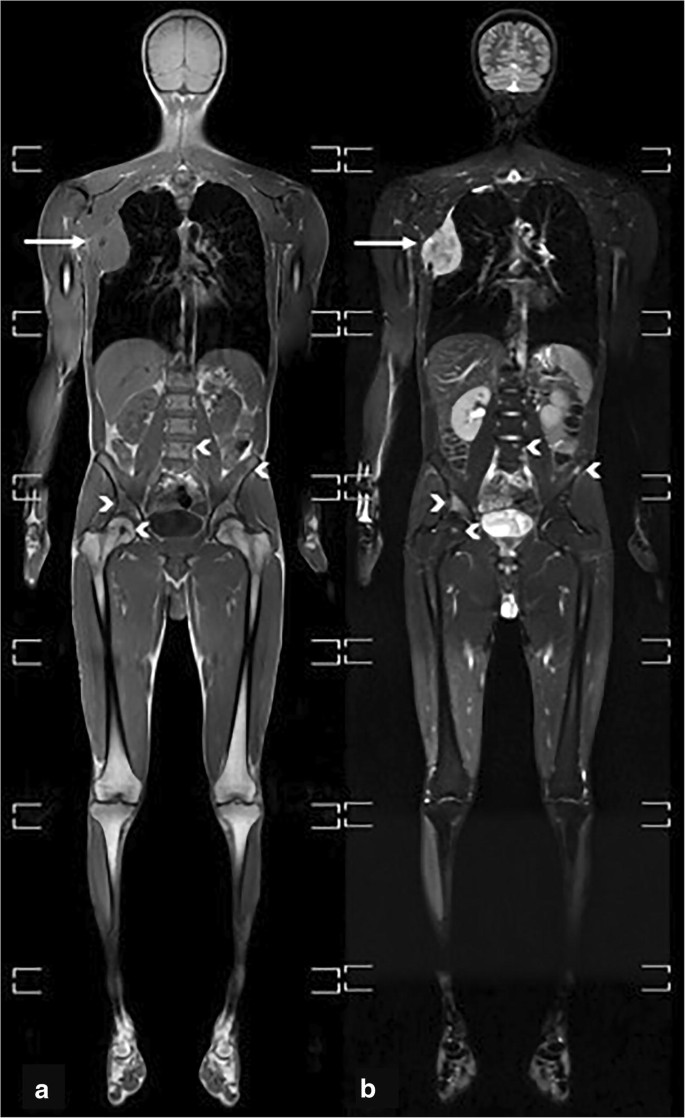

Whole Body Mri Scans T1 Weighted Images And Transverse Sections Of Download Scientific Diagram